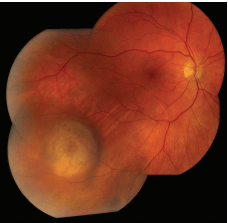

Choroidal Nevus

A choroidal nevus (plural: nevi) is typically a darkly pigmented lesion found in the back of the eye. It is similar to a freckle or mole found on the skin and arises from the pigment-containing cells in the choroid, the layer of the eye just under the white outer wall (sclera). (Figures 1 and 2).

SYMPTOMS

Most commonly, a choroidal nevus does not cause any symptoms and is found on routine eye exam. However, sometimes nevi under the center of the retina (the macula) can cause blurred vision. When a nevus causes degeneration or dysfunction of the overlying RPE, fluid may accumulate under the retina or abnormal blood vessels (choroidal neovascularization) may develop and bleed or leak fluid.